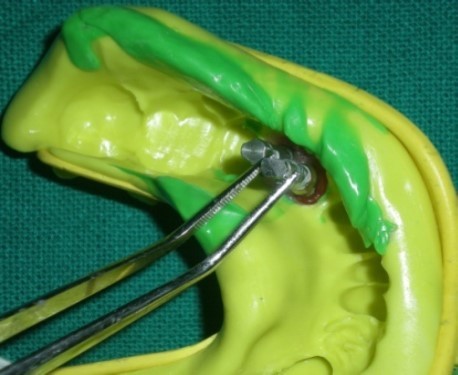

Attach the implant analogue (IA Implant analogue, AlphaBio, Israel) to the respective copings with long connecting screw. Verify the accuracy of the impression by checking the movement of the impression coping by holding with tweezer (Figure 6). If any movement of the analogue-coping assembly occurs, impression should be repeated again.

Figure 6.Check the movement of impression coping by holding with tweezer.